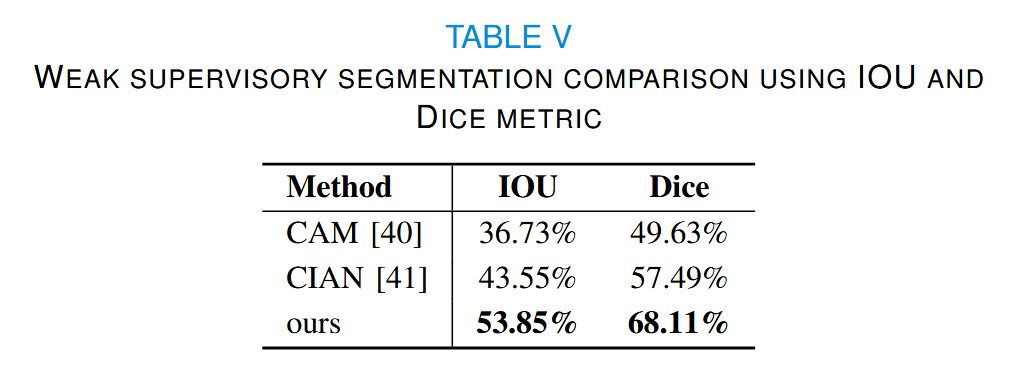

4.4 Weakly supervised segmentation

此外,我们与其他弱监督分割方法进行了IOU和Dice的比较,结果表明我们的方法表现更优,如表V所示。

CAM [40] 表示在弱监督分割任务中生成种子点的方法,

CIAN [41] 则是基于优化CAM的重新训练方法。

这两种方法的阈值均设置为0.6。